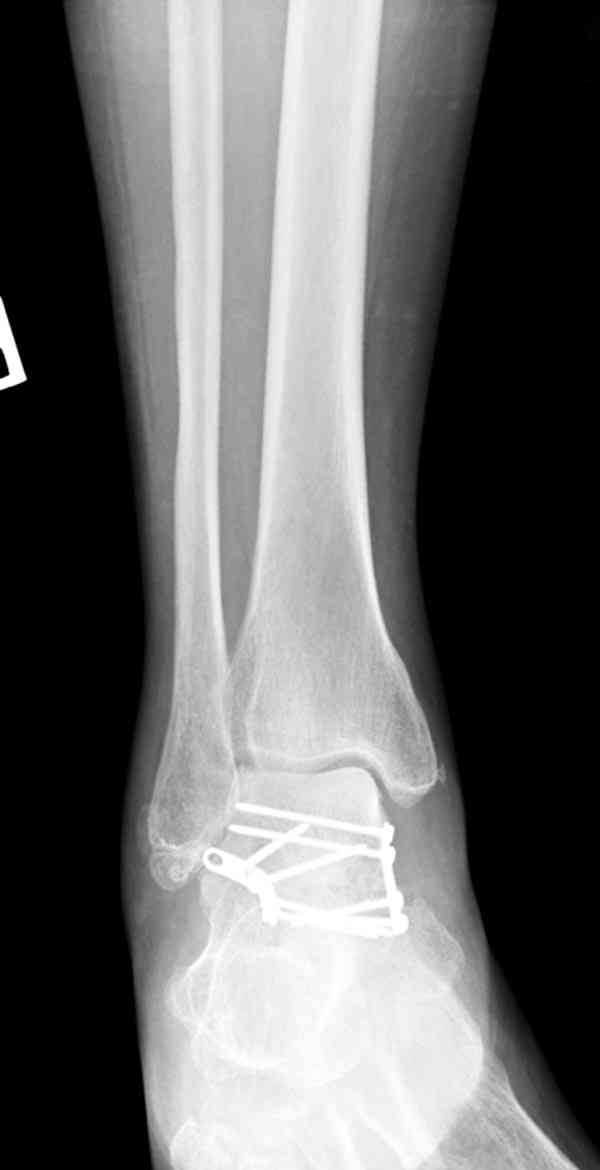

В вашем случае доступ через перелом медиальной лодыжки, обычный доступ через остеотомии лодыжки, где имеется возможность прямой репозиции тарана, после фиксации шурупами, лодыжки фиксируются обычным 2х лодыжечным методом.

Случай с множественным оскольчатым переломом тарана оперированный из двойного доступа.

Через 8 мес.: